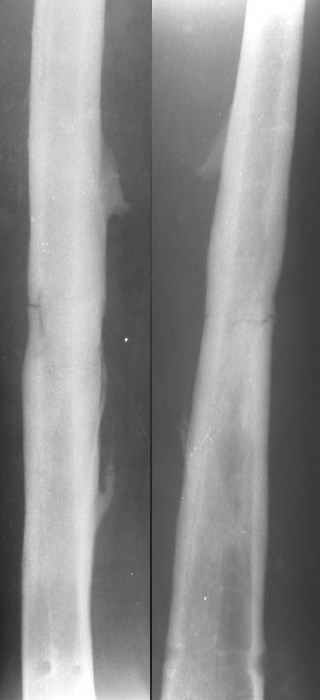

Уважаемые коллеги.Пациентка 18 лет поступила через 6 недель после блокированного остеосинтеза бедра с жалобами на повышение Т до 38гр., незначительной интенсивности боли в Н/3 оперированного бедра, возникающие при движениях (сгибание свыше 90гр.) в коленном суставе. Местно: признаков воспаления, отёка не найдено, пальпация безболезненная. ОАК - N, в моче - капли жира. Картину расценили как проявление жировой эмболии, в течении недели проводилась инфузионная терапия, дезагреганты, постельный режим. Т - N, в моче - жир сохраняется. История болезни этой пациентки началась 5 лет назад с перелома бедра в ДТП, оперирована 2-ы пластиной накостно в одной из больниц нашего города, 2-ы перелом импланта, после последнего раза поступила в нашу клинику, где был выполнен блокированный остеосинтез. Через два года гвоздь удалён (по просьбе больной), Rg-сращение. Через год после удаления рефрактура от незначительной травмы, остеосинтез гвоздём с блок., в раннем послеоперац. периоде жировая эмболия, после купирования амбул. лечение.Прошу советов по дальнейшему лечению. перелом пластины после I опер |  перелом пластины после II опер |  III опер. |  рефрактура через год после удаления штифта |  через мес. после последнего остеосинтеза |